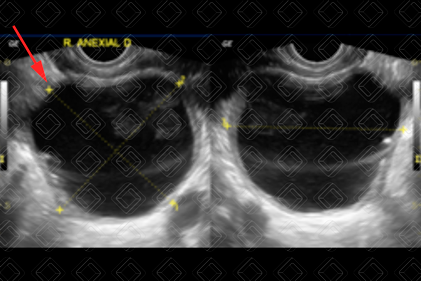

Descrição das figuras 3 e 4: Paciente do sexo feminino, 19 anos. Ultrassonografia da pelve feminina, estudo suprapúbico, evidenciando formação ovalada, anecoica, medindo 3,0 cm, no ovário esquerdo, devendo representar cisto funcional (seta vermelha).

Cistos simples (figuras 1, 2, 3 e 4): Se apresentam na ultrassonografia pélvica como lesões anecoicas, com reforço acústico posterior, unilocular, sem septos ou componentes sólidos no seu interior e não vascularizadas. A maioria dessas lesões é de cistos funcionais e ocorre na pré-menopausa. No entanto, vale a pena lembrar que, apesar de raras, essas lesões também podem ocorrer na pós-menopausa. Diante de uma lesão ovariana cística simples, o acompanhamento é sugerido baseado nas suas dimensões.